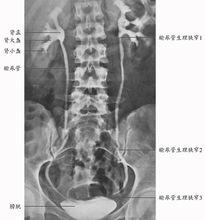

靜脈腎盂造影靜脈腎盂造影(IVP):又稱排泄性尿路造影。系由靜脈注入含碘造影劑,造影劑主要通過腎臟排泄,經過腎小球過濾、腎小管濃縮後,自腎集合管排出後兒顯影。含有造影劑的尿自腎盞排到腎盂、輸尿管及膀胱時均可顯影。成人在注射造影劑後,壓迫輸尿管,在第7、15、30分鐘各拍片1張。兒童應減少照相次數,除平片外,於注藥後第3~5分鐘,拍腎臟照片1張,第7~12分鐘拍第2張,包括腎臟、輸尿管和膀胱。

靜脈腎盂造影除了能了解尿路是否有功能性或器質性異常外,還可以判斷腎臟的排泄功能,腎影大小、形態,腎盂、腎盞有無瘢痕、變形等,並對鑑別腎盂腎炎、腎結核、腎腫瘤也有一定的意義。凡在臨床上懷疑有尿路異常者,如男性青壯年人、兒童患者、反覆發作的女病人,尿路感染並有菌血症者、腎絞痛者,或有腎結石史者,均應作靜脈腎盂造影檢查,對於慢性腎盂腎炎已有腎功能不全者,以往認為不宜做IVP,但近年來,經實踐證明並非禁忌症,可套用大劑量靜脈滴注作腎盂造影。